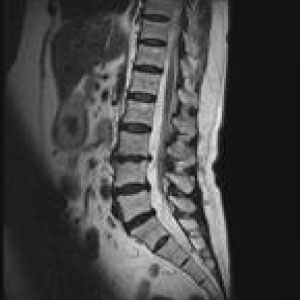

MRIはMagneticResonanceImageの略で強い磁石と電波によって人体の構造を見ることが出来る検査です。

頭部領域から脊椎・関節・骨疾患、腹部に至るまで全身部位の診断に役立ちます。

脳梗塞、脳腫瘍、脳動脈瘤、頚髄症、椎間板ヘルニア、脊柱管狭窄症、脊椎圧迫骨折、腱板損傷、各関節靭帯損傷、半月板損傷、骨壊死、肉離れ、骨腫瘍、軟部腫瘍、炎症、など